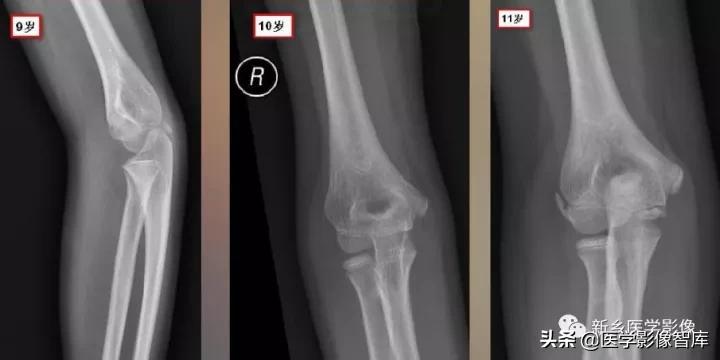

肘关节骨骺

现在简单了,只要记住CRI TOE1-3-5-7-9-11就行了:

- Capitellum (appears age 1-2)肱骨小头1 year - Radial Head (appears age 2-4)桡骨小头 3years- Interanal epicondyle (appears age 4-6)内上髁 5years- Trochlea (appears age 8-11)滑车 7years- Olecranon (9-11 years)鹰嘴 9years- External epicondyle (appears age 10-11)外上髁 11years